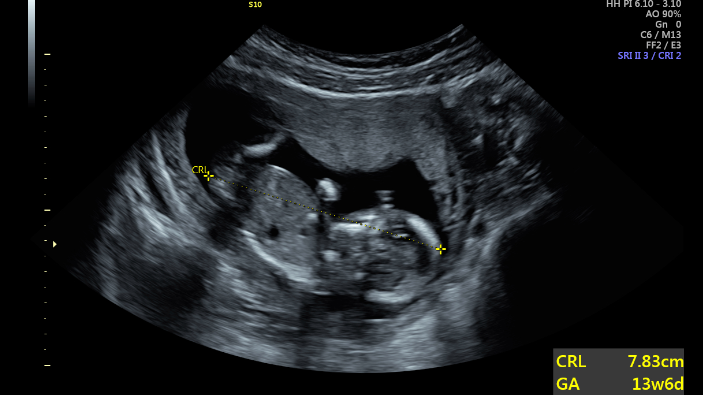

It was the ultrasound that changed things. When she heard the heartbeat, “I heard life. I even heard something divine,” Jasmine shared. “This is not something to get rid of; it’s very real.” It was then Jasmine knew she could not abort. She was eager to return to the Pregnancy Center.

Through it all, Jasmine blossomed. Her self-esteem grew and she now knows her self-worth. Even as the Center was helping her find stable ground, she was already finding ways to help others. Jasmine’s journey is a beautiful, encouraging testament of what can happen when women have the resources and practical support to create a brighter future for themselves and their children. And it’s a reminder of the impact one ultrasound can have in changing – and saving – a life.